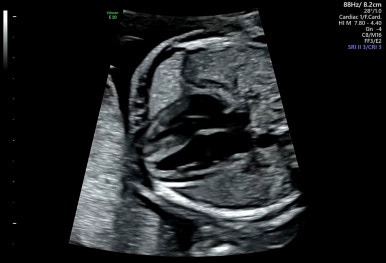

28주 1일

입체초음파로 태아의 얼굴을 볼 수 있는 시기이다!

제일 기다렸던 때이고, 다행히 태아 얼굴을 볼 수 있었다.

다음 초음파는 3주 뒤, 그 다음 9개월 차 부터는 2주 간격으로 검사한다고 한다.